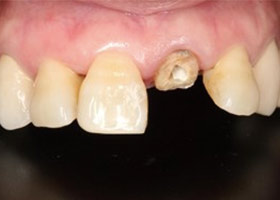

植牙後,立即利用舊牙套轉換成臨時性假牙。

植牙後,裝上臨時性假牙X光片。